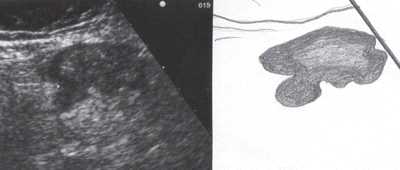

Рис. 4 Компьютерная

томография с контрастированием: дивертикулярная болезнь сигмовидной кишки (S),

осложнившаяся с образованием абсцесса (А), содержащего большое количество газа

(стрелка).

Весьма информативный метод выявления

дивертикулёза, дивертикулита и паракишечного инфильтрата - УЗИ брюшной полости.

При этом хорошо определяются сами дивертикулы, их локализация, наличие в них

воспалительных осложнений.

Рис.5 Эхографическая

картина дивертикулита. Трансабдоминальное исследование линейным датчиком 7,5 МГц.

а - продольный срез; б - поперечный срез.